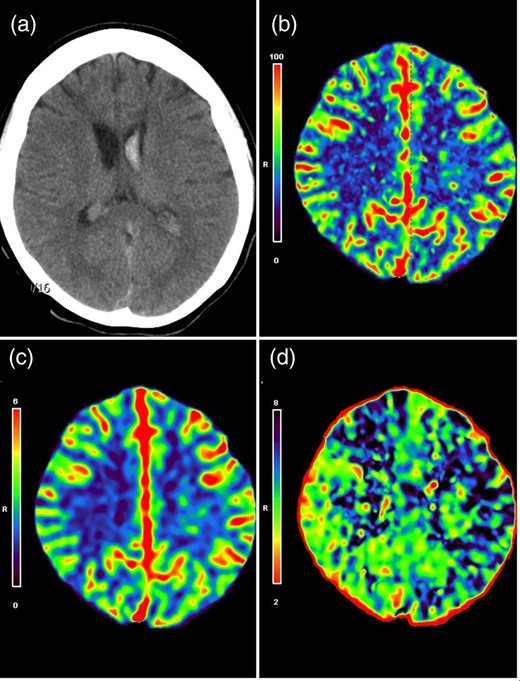

A 20-year-old female patient was admitted with a sudden onset of severe headache. Neurological examination revealed no neurological deficits, but brain computed tomography (CT) revealed an IVH mainly on the left side (Fig. 1a). This finding indicated that the bleeding point was more likely located on the choroidal arteries. Perfusion CT further demonstrated a relative hypoperfusion status in the left hemisphere, as evidenced by an increased mean transit time (MTT) in the left fronto-parietal region (Fig. 1b–d). An external ventricular drain was placed on the right side to decompress the ventricle.

(a) CT scan showed primary IVH predominantly on the left lateral ventricle. CT perfusion maps demonstrated symmetric cerebral blood flow (b) and cerebral blood volume (c), but an increased MTT on the left side (d), indicative of a relative hypoperfusion on the left hemisphere.